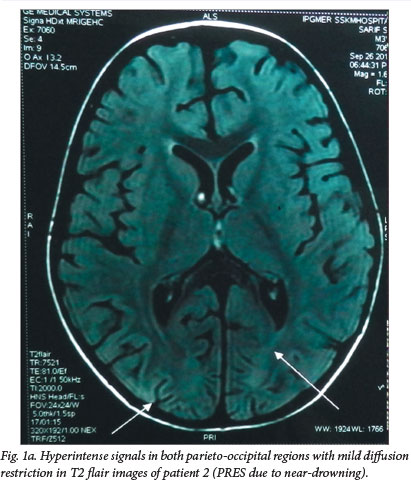

Posterior reversible encephalopathy syndrome (PRES) (also called reversible posterior leukoencephalopathy syndrome) is a mostly transient and reversible neurological disorder clinically characterised by headache, seizures, blindness and altered consciousness associated with radiological abnormalities in the posterior white matter. Hypertension has been implicated as the most common association. We report four cases of PRES associated with non-hypertensive causes together with a review of the literature. Two cases occurred following cerebral anoxia due to accidental strangulation and near-drowning, respectively. The third patient, a child known to have E-β thalassaemia, presented with transient encephalopathy following blood transfusion but involving the anterior brain rather than the posterior part classically described in PRES. The fourth patient developed PRES while recovering from toxic epidermal necrolysis syndrome. None of these four cases had hypertension at any point during their illness.

Posterior reversible encephalopathy syndrome (PRES) is characterised by the acute onset of transient and usually reversible alteration of consciousness, seizures, headache and visual disorders, and is associated with abnormal neuroimaging findings mostly in the parieto-occipital cortex.[1] We describe four children with PRES with novel aetiological associations. The first two had hypoxia following accidental strangulation and near-drowning, respectively. The third, a thalassaemic child receiving regular blood transfusions, had PRES following one such transfusion episode. The fourth child had PRES while recovering from toxic epidermal necrolysis syndrome (TENS). In addition, the child with thalassaemia had involvement of the anterior brain instead of the classically described posterior parts of the brain.

Key features of the four cases are detailed in Table 1. PRES in cases 1 and 2 appears to have been precipitated by brain hypoxia, as a result of strangulation and drowning, respectively. The third child was on regular blood transfusions and PRES occurred following one such blood transfusion. The neuroradiological findings of the third child differed as she had involvement of the anterior brain rather than the more commonly reported posterior brain. The fourth child was admitted initially with a diagnosis of TENS. She had 80% involvement of the body surface area along with oral, genital and conjunctival mucosal lesions. Hence, her SCORTEN score[2] was 4, giving her mortality risk of 58.3%. She also developed septicaemia with blood culture growing Acinetobacter baumanii sensitive to colistin. She was on the road to recovery, having responded to intensive supportive care and IV antibiotics, when she developed features of PRES on day 12 of admission.

PRES (also termed reversible posterior leukoencephalopathy syndrome), first described in 1996, is a neurological disorder clinically characterised by headache, seizures, blindness and altered consciousness associated with radiological features of oedema, most often involving the white matter in the posterior regions of the cerebral hemispheres. The oedema is often more pronounced bilaterally in the parieto-occipital regions, but may sometimes spread to the basal ganglia, brainstem and cerebellum. The oedema is usually completely reversible with resolution of clinical symptoms and radiological features. This is in contrast to changes resulting from hypoxic-ischaemic insults, which show permanent radiological signs. PRES was first reported by Hinchey et al.[1] in 1996 after an observational study of 15 patients. Since then, a few case reports and some case series have been published.[3-6]

The exact pathophysiology of PRES has yet to be elucidated. It has been postulated that the clinical features might be due to sudden disruption of the autoregulatory mechanisms of the central nervous system vasculature, resulting in endothelial dysfunction and breakdown of the blood-brain barrier. Sudden elevation of blood pressure could be one of the factors leading to this disruption. There is a predilection for involvement of posterior circulation territories, thought to result from the relatively sparse sympathetic innervations of the vertebrobasilar circulation, but there are reports of involvement of the anterior brain, brainstem, basal ganglia, corpus callosum and cerebellum (atypical magnetic resonance imaging (MRI) findings).[1,6] The second postulated cause for PRES is a direct cytotoxic effect on the cerebrovasular endothelium.[6]